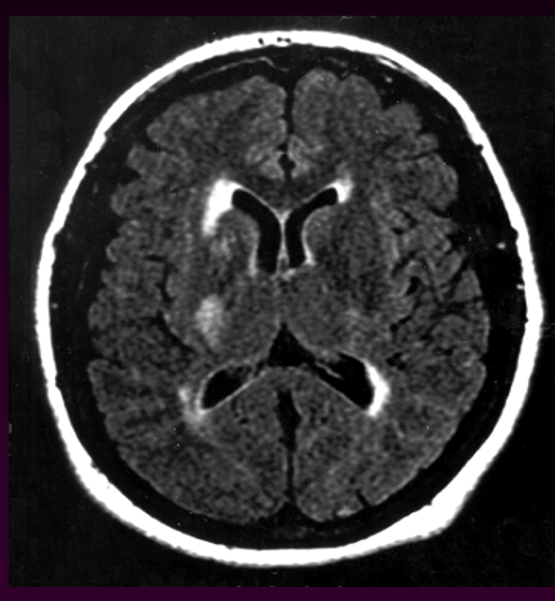

Chẩn đoán dễ dàng bằng CT

Xuất huyết dưới nhện

- Thường do vỡ phình mạch dạng túi

- Chủ yếu ở tuần hoàn não trước